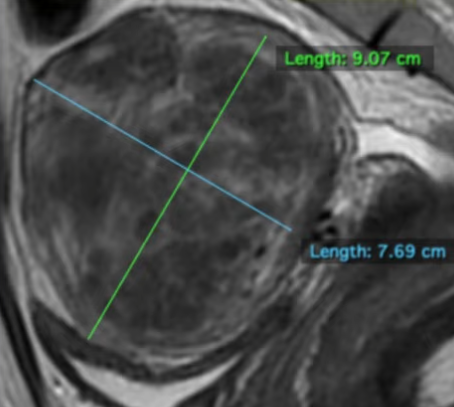

MRI